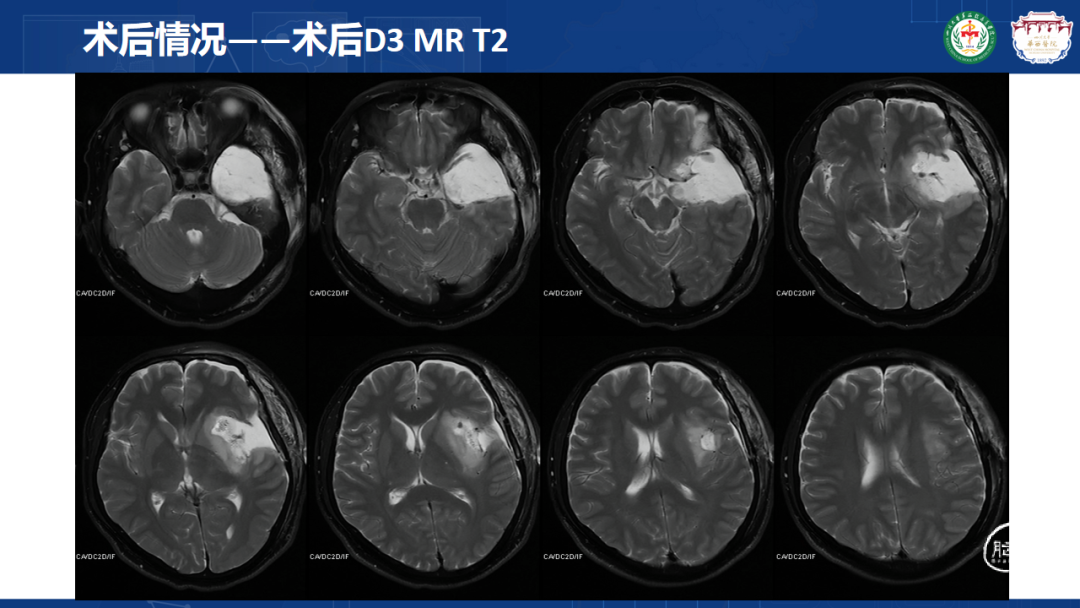

来自四川大学华西医院的曾云辉医师带来《岛叶胶质瘤手术及综合治疗》。该病例是一名41岁男性IT从业者,表现为头晕、右侧肢体麻木伴幻听,MRI显示左侧额颞岛叶占位累及海马头,DTl重建显示肿瘤包绕大脑中动脉分支。术中使用无牵拉技术联合多模态监测,经颞叶皮层造瘘切除病灶,术中重点保护侧裂静脉及M2段穿支血管。术后病理确诊为IDH突变型少突胶质细胞瘤(WHO 3级),规范实施同步放化疗联合6周期替莫唑胺辅助化疗。随访显示肿瘤控制良好,患者神经功能完整并恢复工作。